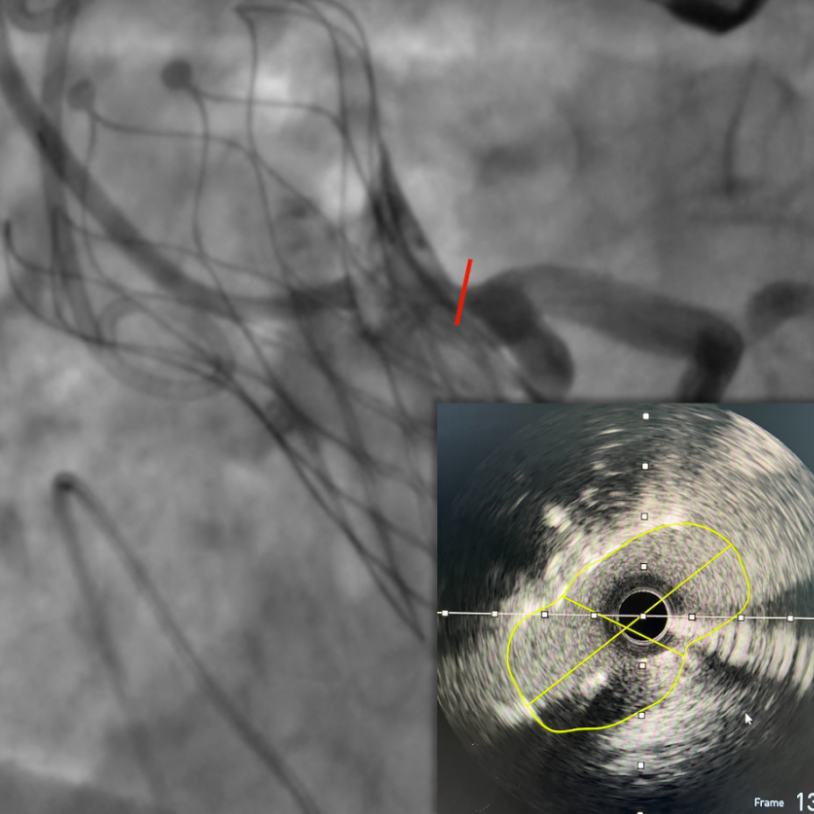

图片

IVUS检查提示因原瓣叶遮挡,左冠开口受阻,最窄处残余缝隙0.66-0.82mm。

复查左冠开口面积恢复至12.76mm2

术后经导管同步测压,跨瓣压差由70mmHg,改善至术后0mmHg。经食道超声显示VitaFlow®瓣膜位置固定,无瓣周漏,瓣膜形态良好。再次通过IVUS评估左侧冠脉开口面积恢复至12.76mm2,患者生命体征平稳并监护。

主动脉瓣四叶畸形 (QAV) 是一种极为罕见的先天性心脏瓣膜病,据报道其尸检发病率为0.00028-0.00033%。超声心动图检出率为 0.0059-0.0065%。在我中心开展的TAVR病例中,遇到的一例四叶瓣,且伴有钙化及冠脉开口低的特征,评估时要注意冠脉阻挡的风险。本病例从CT根部结构剖析,右无窦间的窦相对偏小不对称,瓣叶严重增厚冗长。24mm的瓣环最终选择了Downsize策略选择了TAV21mm瓣膜,对应使用18mm球囊进行预扩,最终植入21mm瓣膜后很好的封住瓣环及流出道,无反流,无压差,血流动力学稳定。然而对释放完瓣膜后后期处理冠脉上VitaFlow®特殊的大网眼设计人工瓣膜,使得瓣周及瓣内开窗入路指引导管得以顺利到位,最大限度保障了冠脉开口的安全性。IVUS也为植入冠脉保护支架提供了精确判断和引导。经过微创介入技术,实现了主动脉瓣和动脉导管未闭一站式介入治疗。